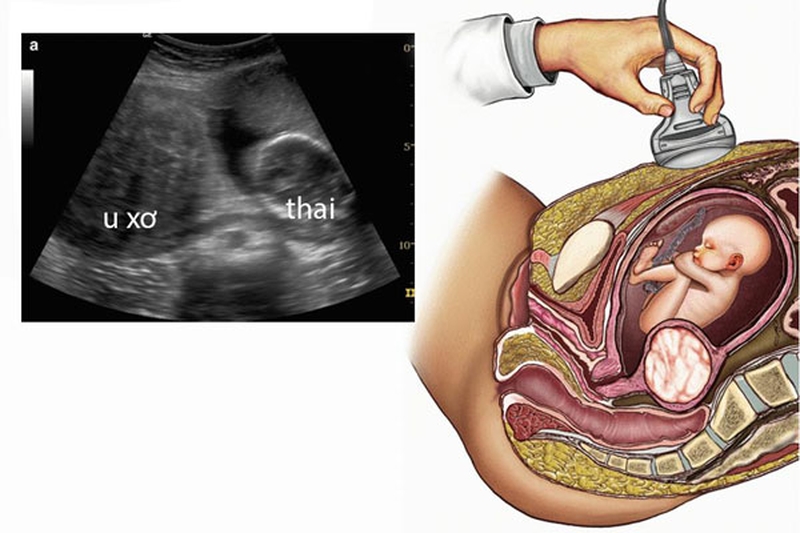

Ước tính từ 40% đến 60% phụ nữ mắc phải các khối u cơ trong tuổi 35. Và con số này nâng lên đến 80% ở tuổi 50.Tuy nhiên việc phát hiện khối u xơ tử cung trong thai kỳ là tương đối khó.

Bởi rất khó để phân biệt sự dày lên của cơ tử cung là do u xơ hay do ảnh hưởng của thai kỳ. Hầu hết phụ nữ được chẩn đoán mắc u xơ đều có thai như bình thường, chỉ có một số trường hợp nhỏ có thể gây ra tình trạng nghiêm trọng đối với các mẹ bầu.

Có thai khiến quá trình chẩn đoán u xơ tử cung khó khăn hơn, ngoại trừ trường hợp khối u to từ 6cm trở lên.